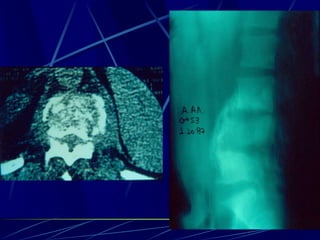

Infections of the spine

Φυματίωση της σπονδυλικής στήλης